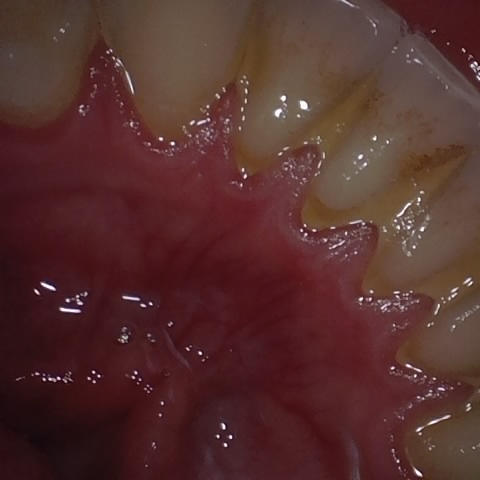

Annotated as "Good"

Original Image Rendering Image